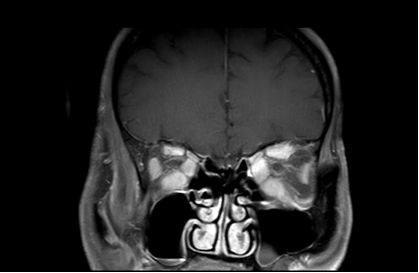

影像学检查:MRI